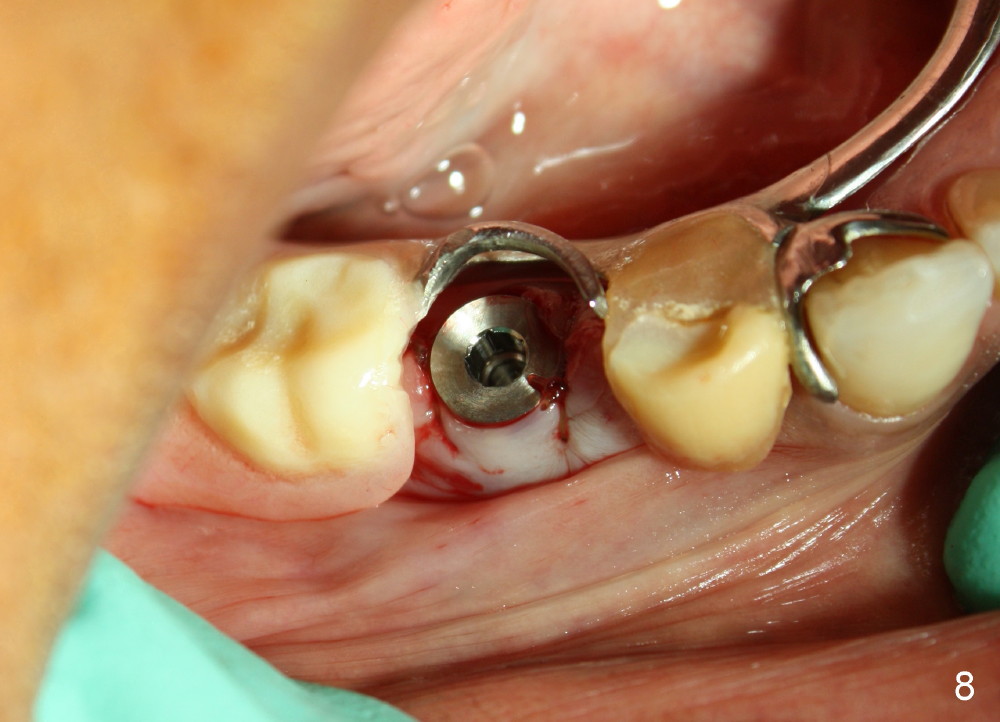

To be safe, immediate implant is planned to be confined to the socket. To achieve primary stability, the largest implant is to be used. The root of the extracted tooth is 5 mm mesiodistally and 6.5 mm buccolingually. The buccal plate is thin. Drills are used minimally, mainly lingually, whereas osteotomy is finished by taps. The first PA is taken when 6x14 mm tap is inserted (Fig.5). There is some distance between the tap and the bottom of the original socket (between black arrowheads). The tap is engaged to the wall of the socket (white arrowhead). The second PA is taken when 6x14 mm implant is initially inserted (Fig.6). There is still space to advance the implant (Fig.6 between black arrowheads). Fig.7 shows the final position of the implant. The implant threads are embedded into the bone (white arrowheads). The insertion torque is over 60 Ncm. When the partial is placed, the implant does not look to be over engineered. There is no sign or symptom of paresthesia or infection (Fig.9, 9 days postop). The gingiva is healthy around the implant 4 months postop (Fig.10). The bone has grown more into the threads of the implant (Fig.11 >, compare to Fig.7).